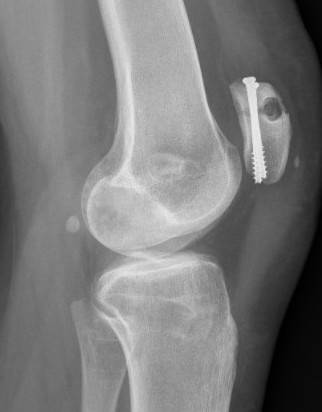

2. Perform TTT (if TTTG > 20)

- incision over TTT

- medialise at least 1 cm

- ensure some element of Fulkerson / anteriorise

- can distalise if patella alta

- secure with screws (2 x small fragment usually sufficient)

- reassess stability